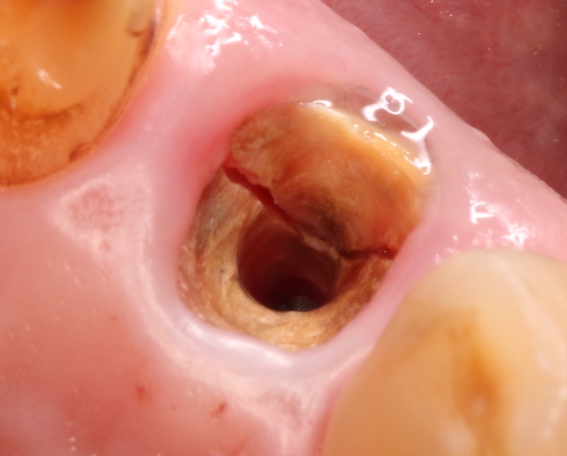

4,歯の破折;根尖性歯周炎と似てはいますが、歯が破折していたり、完全に歯が破折していなくてもひび(クラック)が入っていると、そこに細菌が溜まりそこから感染が起き歯肉が腫れてきます。この場合、抗生物質を服用し腫れを引かす必要があります。その後、抜歯などの処置が必要となってきます。